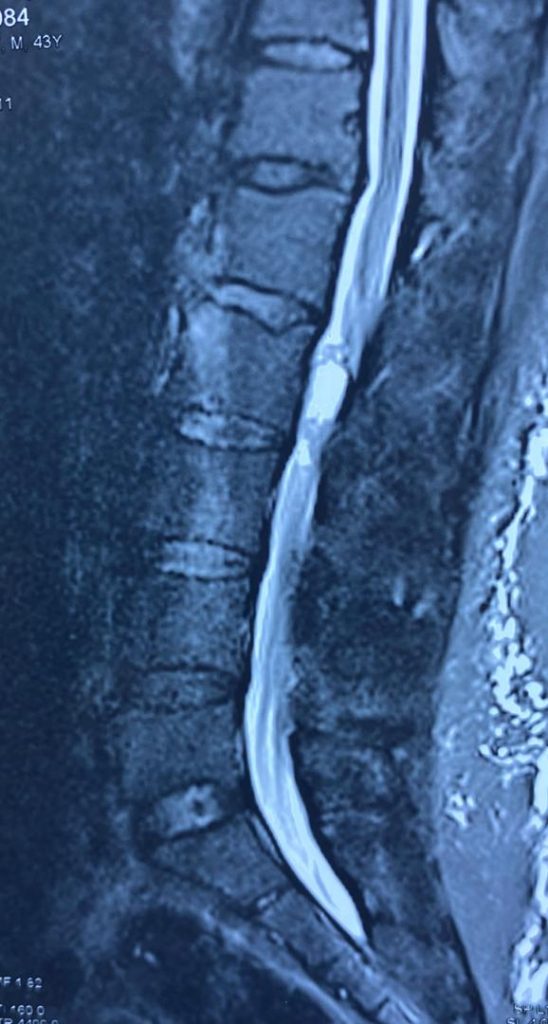

تصاویر قبل از عمل